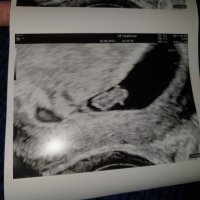

For en fantastisk følelse å få se hjerteslag for første gang i dag!Var kjempenervøs før timen, men det gikk heldigvis veldig bra og det ble målt et lite nurk på ca. 7+3 uker. Ble satt tilbake ca. 2 uker, men det var helt som forventet med forsinket el denne perioden. Lykkerus!!!

Vis vedlegget 406872